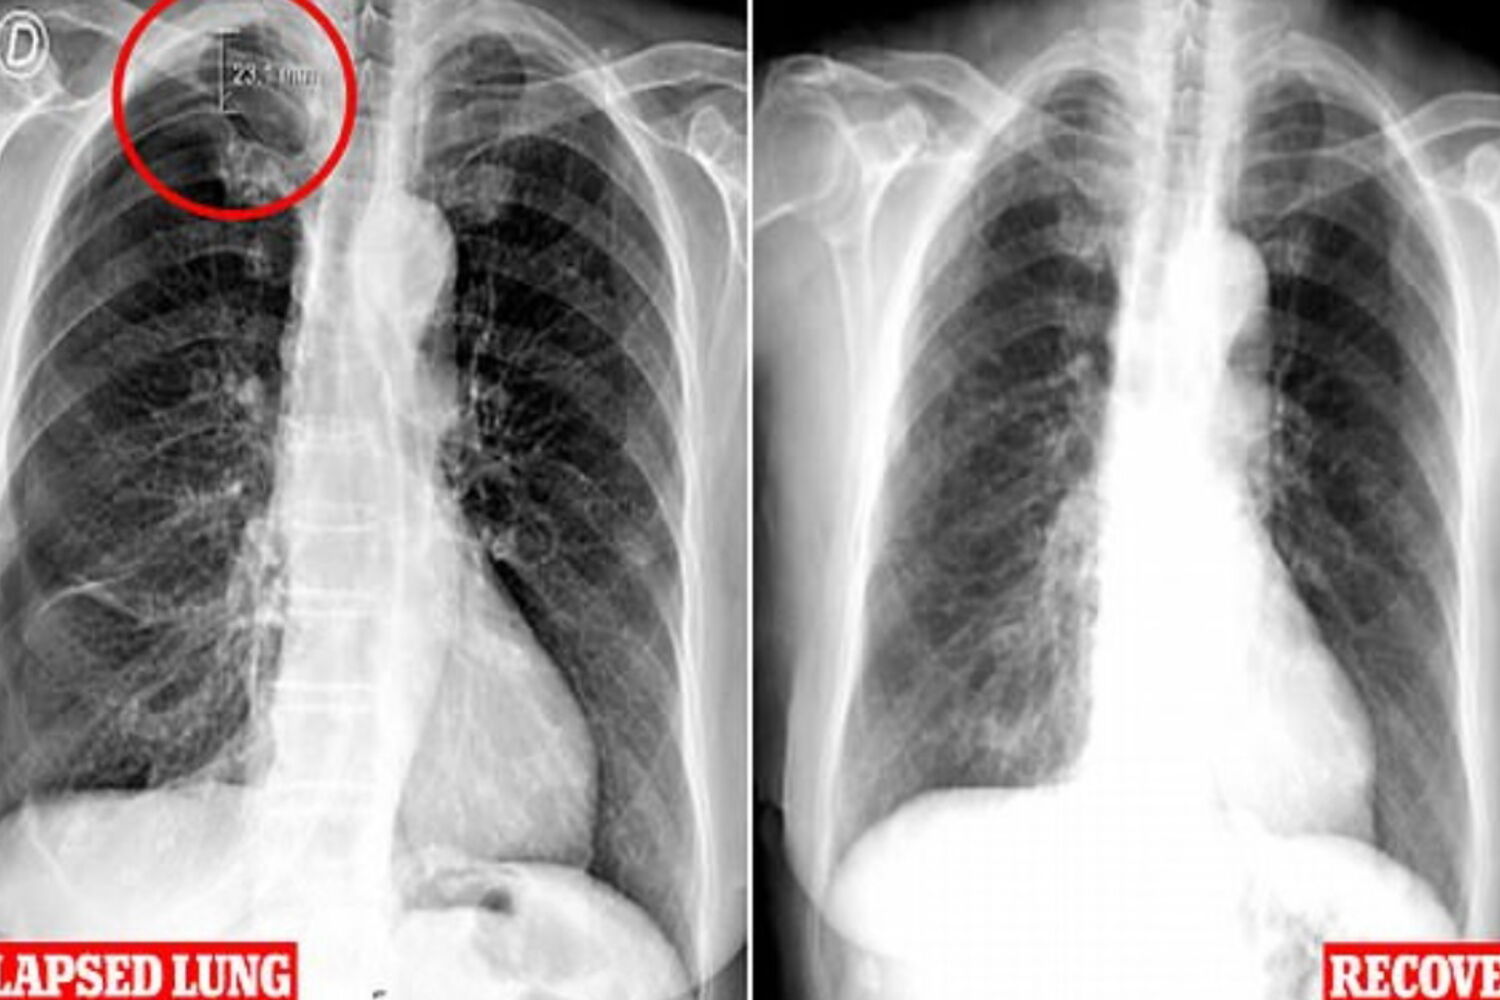

Um tratamento de acupuntura provocou o colapso do pulmão de uma mulher portuguesa de 79 anos, de acordo com os médicos do Centro Hospitalar Universitário da Central de Lisboa.

Os médicos descobriram que parte do pulmão direito teria entrado em colapso e culparam as agulhas usadas na acupuntura.

A senhora teve uma recuperação completa em poucos dias, mas os médicos alertaram que a prática inadequada pode levar a problemas como o risco de vida, segundo jornal britânico Daily Mail.